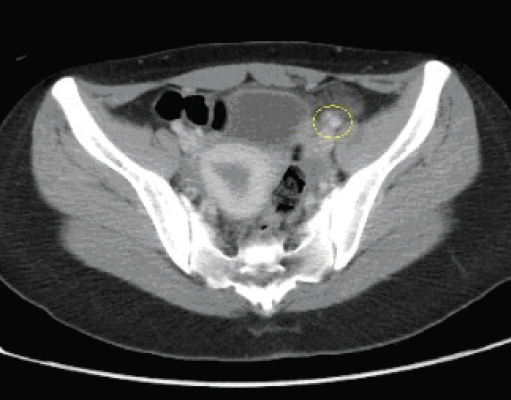

An abdominal computed tomography (CT) scan with oral and intravenous contrast showed a normal appendix, with stranding of retroperitoneal fat adjacent to the sigmoid colon and the proximal ileum representing epiploic appendagitis (Figure). The patient was admitted for conservative management with analgesics; within 2 days, her pain had resolved and she was discharged.

Diagnosis most commonly is with ultrasonography or CT, with the latter being the preferred modality.9 In normal conditions, epiploic appendages are not visible on a CT scan. The characteristic CT finding is a small adipose mass (usually less than 5 cm) surrounded by a hyperdense rim adjacent to the colon.5